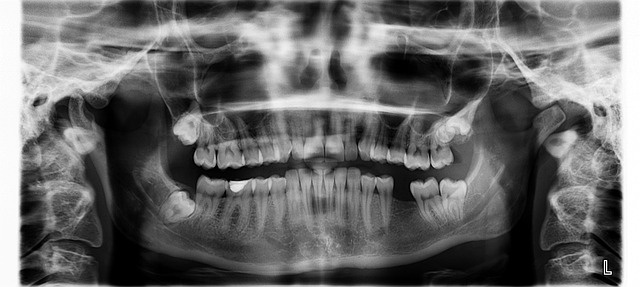

사랑니는 일반적으로 17세에서 25세 사이에 나는 마지막 어금니입니다. 보통 위쪽과 아래쪽 각각 두 개씩 총 네 개가 있습니다. 하지만 사람에 따라 턱 공간이 부족하여 나지 않거나, 매복(치아가 잇몸 안에서 자라난 것)되어 날 수도 있습니다.

사랑니가 문제를 일으키는 경우는 여러가지인데요, 이가 삐뚤게 나거나, 주위 치아에 압력을 가해 통증을 유발하는 경우, 잘 닦이지 않기 때문에 발생하는 충치 등이 생겼을 때 등입니다. 이런 문제들을 해결하기 위해 사랑니는 발치하는 것이 좋습니다. 이 글을 보시는 분들은 사랑니를 한쪽만 뺐을 때의 문제점에 대해서 궁금하시겠죠? 아래로 가보시죠.

많은 사람들이 사랑니를 한쪽만 발치하는 경우가 있습니다. 이런 상황에 대부분의 사람들이 한쪽만 빼면 얼굴의 좌우 대칭이 어긋나서 안면 비대칭이 올 수 있지 않을까? 걱정을 할 것입니다. 4년 전에 저도 그런 걱정을 했습니다. 네이버 지식인 등에 물어보면 치과 전문의들은 사랑니를 한쪽만 뺀다고 안면 비대칭이 오지는 않는다고 답변을 해주는데요, 왼쪽 사랑니만 위, 아래로 빼고 4년을 지낸 후 제 경험으로는 안면 비대칭이 생겼습니다.

비포 사진은 양쪽 사랑니 발치 전, 애프터 사진은 왼쪽 위, 아래 2개의 사랑니를 발치하고 4년 후입니다. 확연히 오른쪽 볼이 커진 것을 느끼실 수 있겠죠? 물론 약간 살이 찌기도 했지만 오른쪽이 왼쪽에 비해 확연하게 통통한 것을 한눈에 알 수 있습니다.

물론 사랑니를 한쪽만 뺀다고 턱의 비대칭이 일어나서 안면 비대칭이 금방 오는 것은 아닙니다. 여기까지는 의사 선생님들 말씀이 맞겠지요. 하지만 제 경험상 한쪽만 사랑니를 뺐을 때 뺀 쪽으로 대부분의 음식을 섭취하게 됩니다. 왜냐하면 사랑니를 뺀 쪽이 공간도 더 넓고, 맛도 더 잘 느껴지고, 씹기에 편리하다고 느껴지기 때문에 무의식적으로 그런 습관을 가지게 됩니다.

그래서 저도 모르게 사랑니가 없는 쪽으로 주로 씹는 행동을 더 많이 하게 되어 얼굴의 근육과 움직임이 한쪽으로만 활성화되게 되는 것이죠. 한쪽만 뺐는데 양쪽으로 동일하게 잘 씹어준다면 상관이 없겠지만 그게 쉽지는 않을 것 같습니다. 확실하게 사랑니가 있는 쪽은 비교적 불편함이 있기 때문입니다.